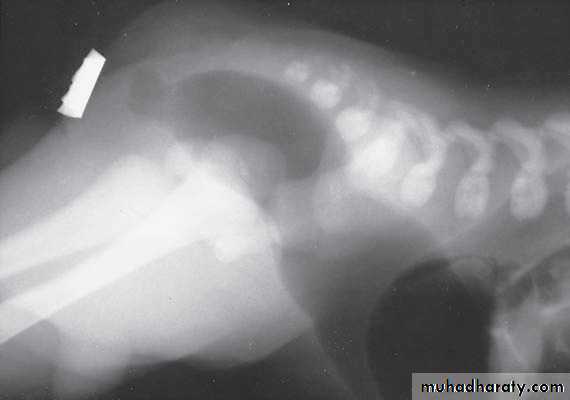

Intussusception